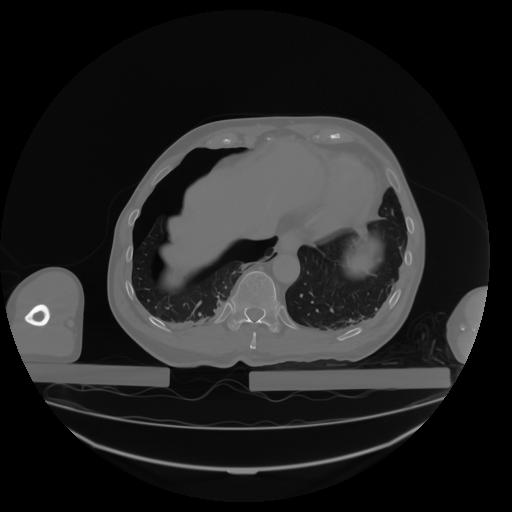

27 CUERPO,CE,Axial,3.0,CUERPO,,